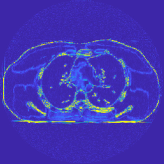

This section compares the reconstruction quality and runtime among the proposed MBIR method, PWLS-ST-, and other three MBIR methods, PWLS-EP, PWLS-DL, and PWLS-ST-. Table I shows that, for both 2D and 3D sparse-view CT reconstructions of the XCAT phantom, the proposed PWLS-ST- model outperforms PWLS-EP and PWLS-ST- in terms of RMSE. In addition, PWLS-ST- using a square transform (of size ) achieves lower RMSE than PWLS-DL using an overcomplete dictionary (of size ) for 2D sparse-view reconstructions. Fig. 3(a) and Fig. 4 show the reconstructed images for 2D and 3D phantom experiments, with different reconstruction models and different number of views. (See the corresponding error maps in the supplement.) The proposed PWLS-ST- consistently gives more accurate image reconstructions compared to other MBIR methods. Specifically, PWLS-ST- has smaller errors in the heart region (see zoom-ins in Fig. 3(a)) of 2D reconstructions than PWLS-DL and PWLS-ST-. In addition, compared to PWLS-ST-, PWLS-DL and PWLS-ST- have some ringing artifacts around the edges with high transition, e.g., edges between air and soft tissues. (See a comparison of profiles of PWLS-ST- and PWLS-ST- in the supplement.) In particular, PWLS-ST- and PWLS-DL give more visible ringing artifacts for 2D reconstruction from fewer views, and PWLS-ST- has these ringing artifacts for 3D reconstructions regardless of the number of views (see zoom-ins in Fig. 4). Table II reports runtimes of different MBIR methods in reconstructing the -views XCAT phantom scan. (FBPConvNet is a non-MBIR method and its runtime for processing a image is approximately one second with a TITAN Xp GPU.) While providing better reconstruction quality, the proposed Algorithm 1 of PWLS-ST- has shorter runtime compared to the algorithms of PWLS-DL and PWLS-ST- in Section III-A. Similar to the PWLS-EP algorithm, the reconstruction time of the PWLS-DL, PWLS-ST-, and PWLS-ST- algorithms can be further reduced by using ordered subsets [51].

Fig. 3(b) shows that when tested on the clinical scan data, the proposed PWLS-ST- method improves reconstruction quality in terms of noise and artifacts removal (e.g., see zoom-ins for soft-issue regions), and edge preservation (e.g., see zoom-ins for bone regions), compared to PWLS-EP and PWLS-ST-. Compared to PWLS-DL, PWLS-ST- achieves comparable image quality, but requires less computational complexity.

The benefit of the proposed PWLS-ST- over PWLS-ST- can be explained when there exist some outliers for some : in (12) gives equal emphasis to all sparse codes – from small to large coefficients that generally correspond to edges in low- and high-contrast regions, respectively – in estimating ; however, PWLS-ST- adjusts to mainly minimize the outliers, i.e., it may not pay enough attention to reconstruct regions with small coefficients. The histogram results in Fig. 1 reveal model mismatch of PWLS-ST- over the iterations. Fig. 3, Fig. 4, and Table I show that PWLS-ST- can moderate model mismatch, and provides more accurate reconstruction than PWLS-ST-.

| (a) 2D fan-beam CT experiments |

| (b) 3D axial cone-beam CT experiments |